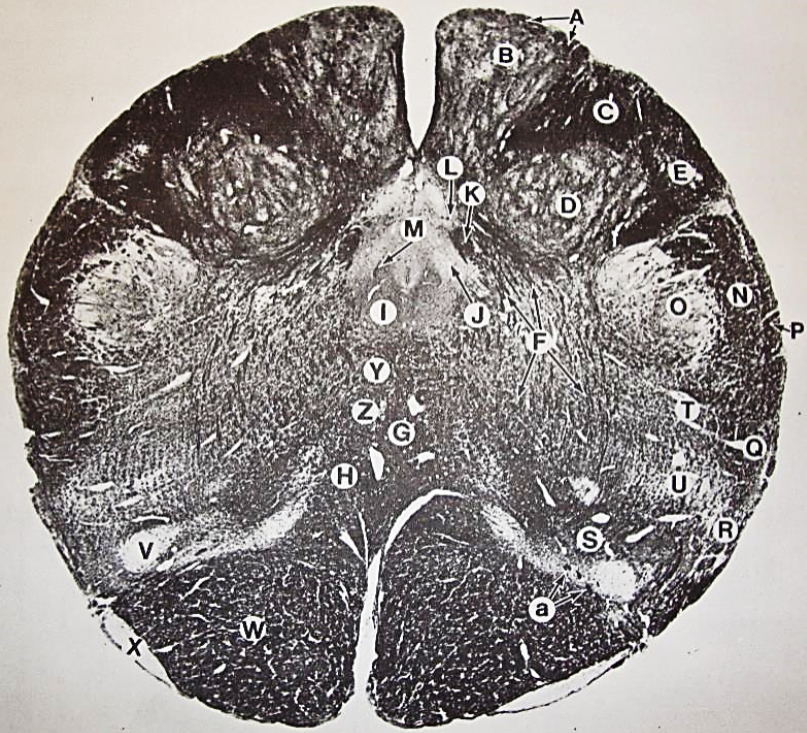

A

Fasciculus gracilis

B

gracile nucleus

C

fasciculus cuneatus

D

cuneate nucleus

E

spinal trigeminal tract

F+G collectively

spinal trigeminal nucleus

H

accessory nucleus

I

pyramidal decussation

J

rubrospinal tract

K

posterior spinocerebellar tract

L

anterior spinocerebellar tract

M

lateral spinothalamic tract

N

anterior spinothalamic tract

O

lateral vestibulospinal tract

P

medial longitudinal fasciculus

Q

tectospinal tract